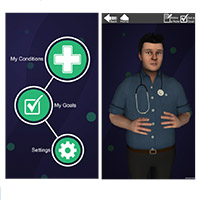

New avatar app to help patients with long term conditions

Posted on 25 January 2016 School of Pharmacy develops new app using its avatars for patient information ...